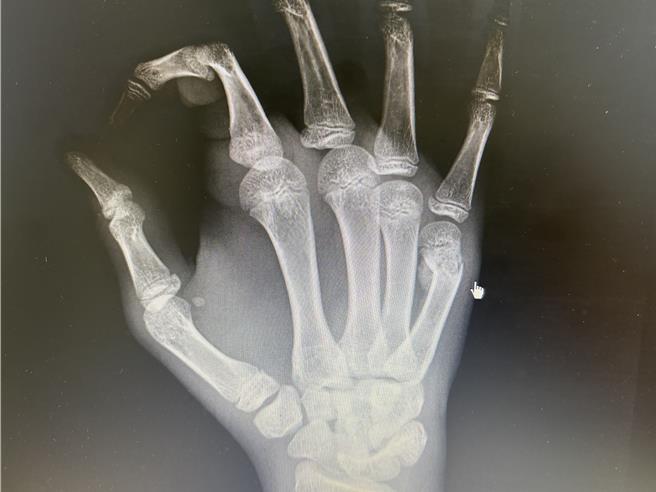

高雄中正脊椎骨科医师廖志祥表示,14岁国中生一时激动握拳撞击墙壁,导致右手掌肿胀疼痛,他本身是羽球选手,当天练球时,痛到无法握球拍,经家人陪同就医检查后,确认其右手掌第5掌骨颈部骨折,骨折弯度达到45度,属于「拳击手骨折」典型症状。

廖志祥说,「拳击手骨折」好发于第5掌骨颈部,因为不正当的施力造成,常见于脾气暴躁男性及拳击初学者,大部分患者经适当治疗后预后良好,不会留下太大的后遗症,保守治疗可以石膏固定或副木保护受伤的手部约6周,等骨折慢慢癒合,患者若严重移位的骨折,就需手术以钢板或钢针固定骨折的部分,